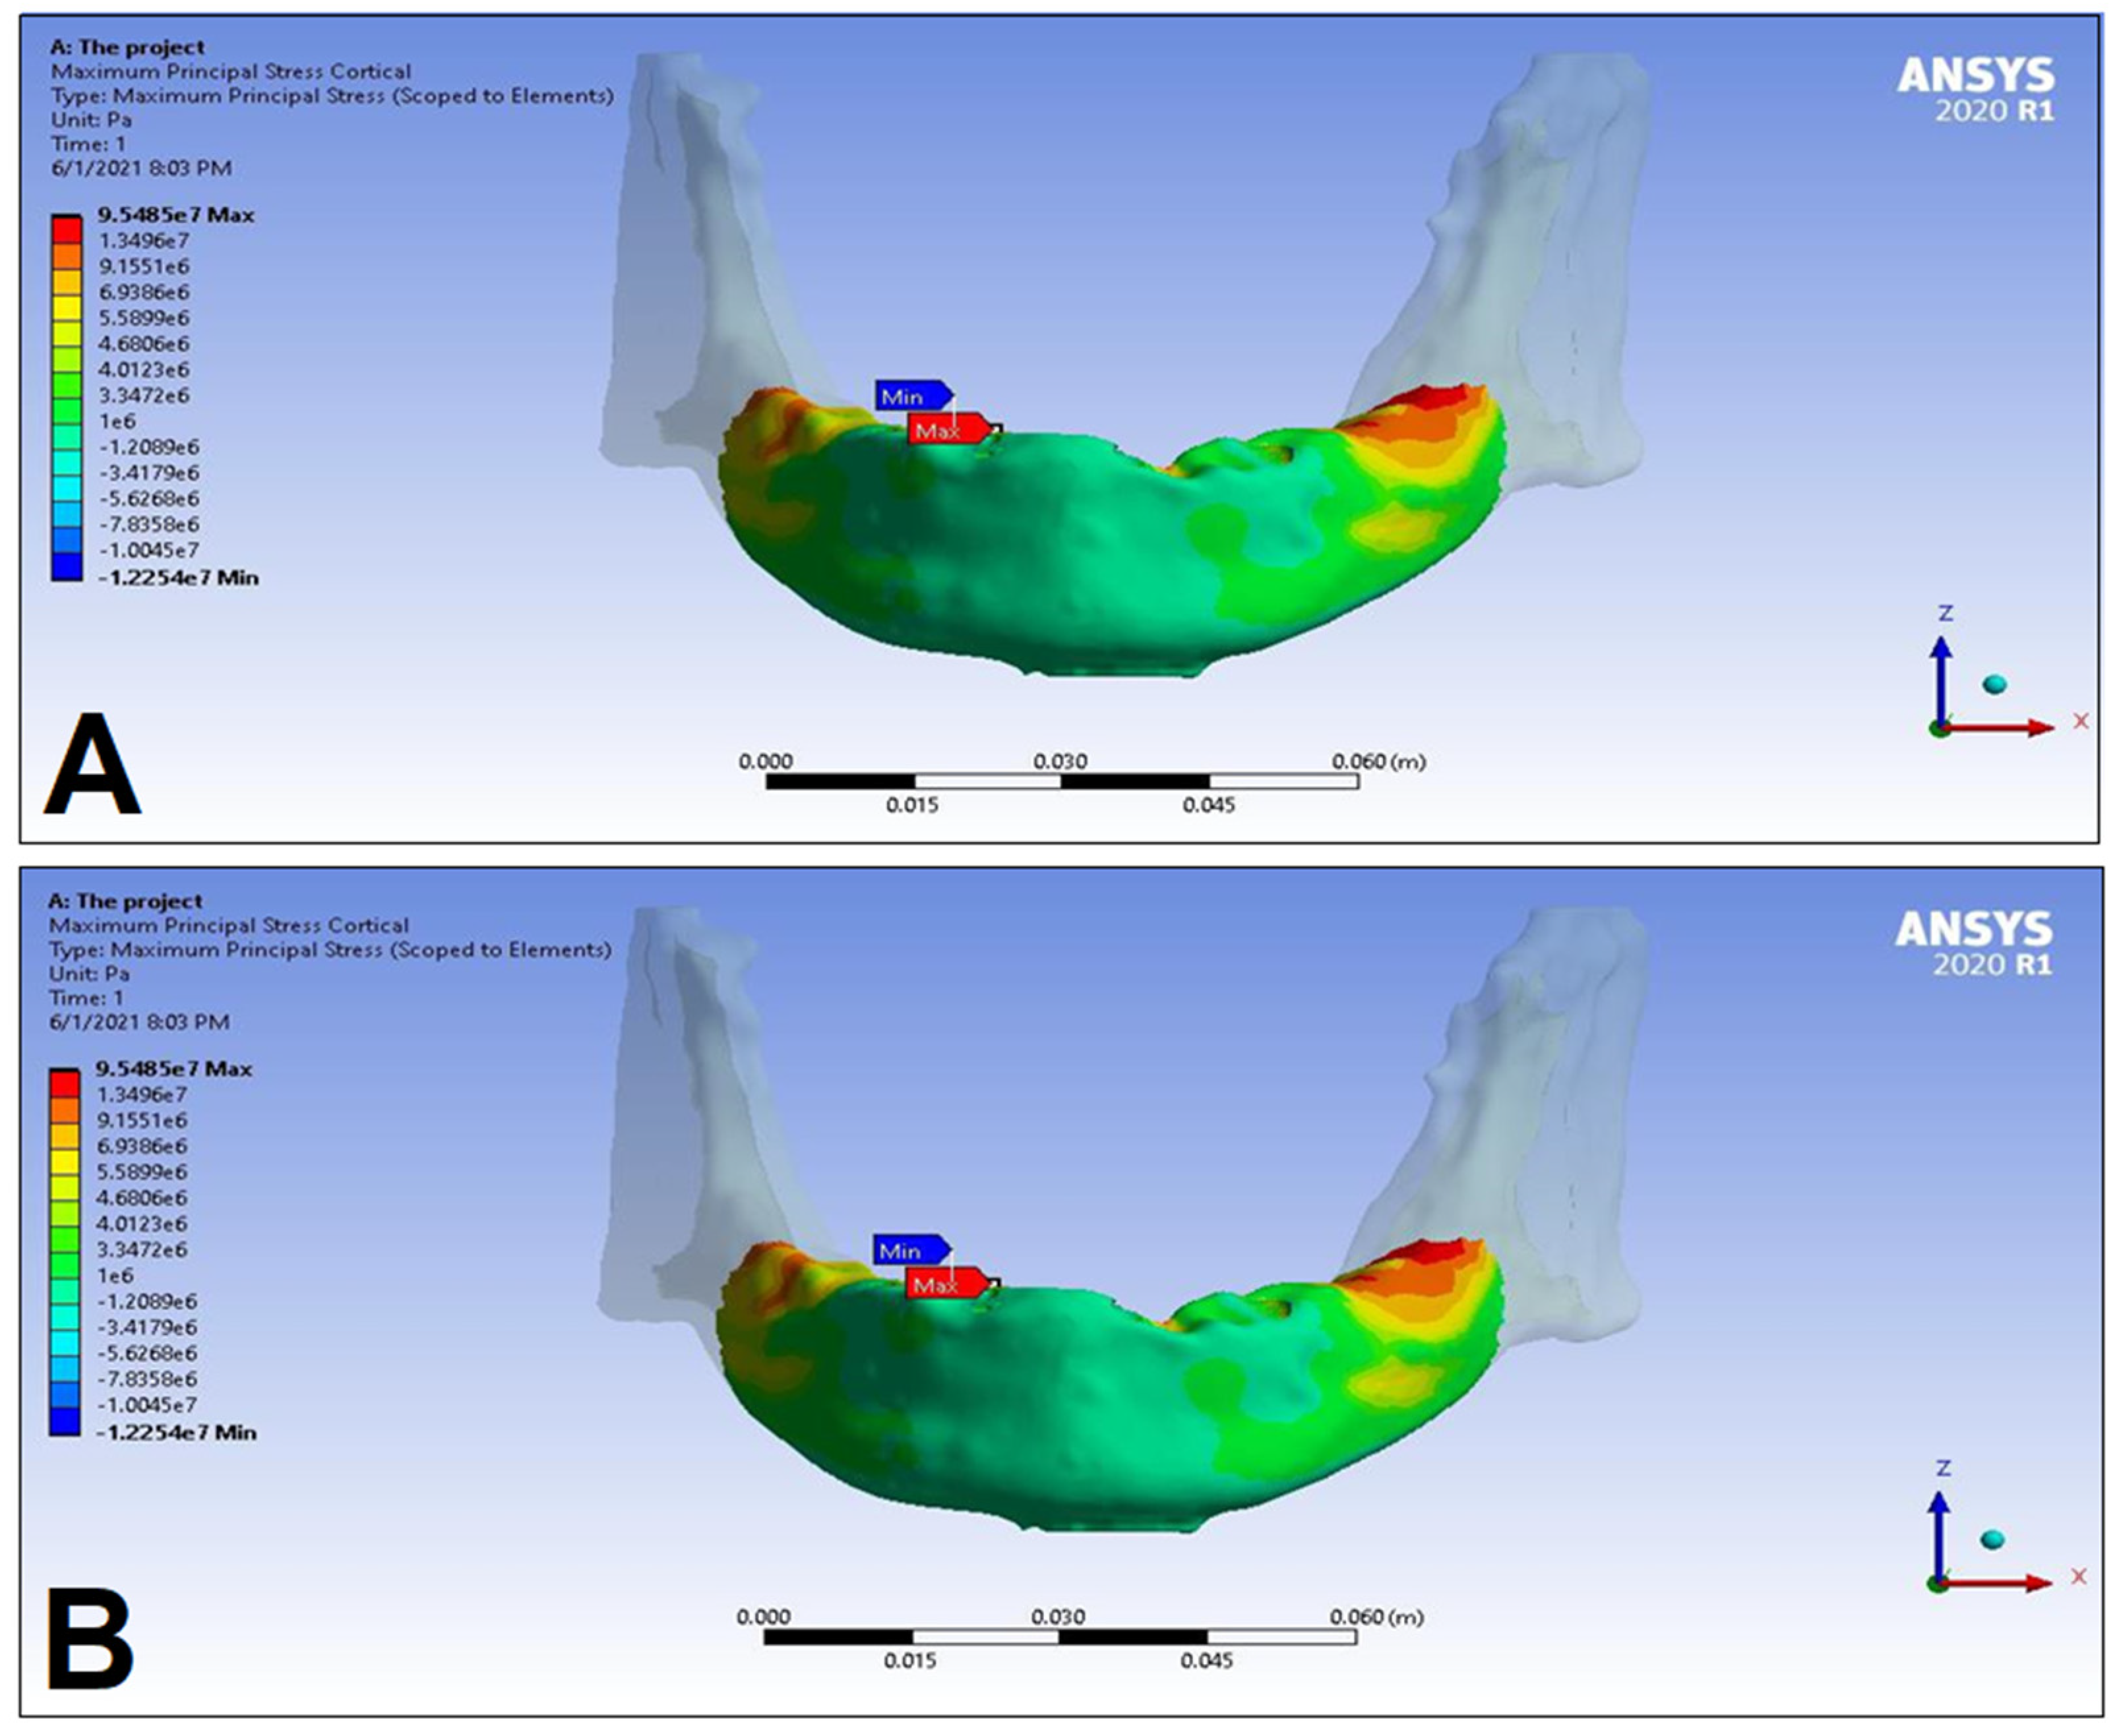

3. Results

| LC1 | LC2 | LC3 | LC4 | ||||||

|---|---|---|---|---|---|---|---|---|---|

| S1 | S2 | S1 | S2 | S1 | S2 | S1 | S2 | ||

| Cortical bone | Pmax [MPa] | 76.39 | 88.51 | 89.57 | 102.98 | 85.63 | 95.48 | 81.02 | 93.15 |

| Pmin [MPa] | −115.30 | −222.76 | −136.4 | −265.35 | −172.30 | −252.61 | −125.20 | −235.32 | |

| Trabecular bone | Pmax [MPa] | 2.49 | 2.24 | 3.03 | 2.62 | 2.95 | 2.52 | 2.92 | 2.59 |

| Pmin [MPa] | −2.81 | −2.89 | −3.34 | −3.38 | −3.25 | −3.25 | −3.49 | −3.52 | |

| Peqv [MPa] | 166.40 | 244.92 | 166.36 | 279.69 | 164.36 | 265.58 | 142.27 | 260.77 | |